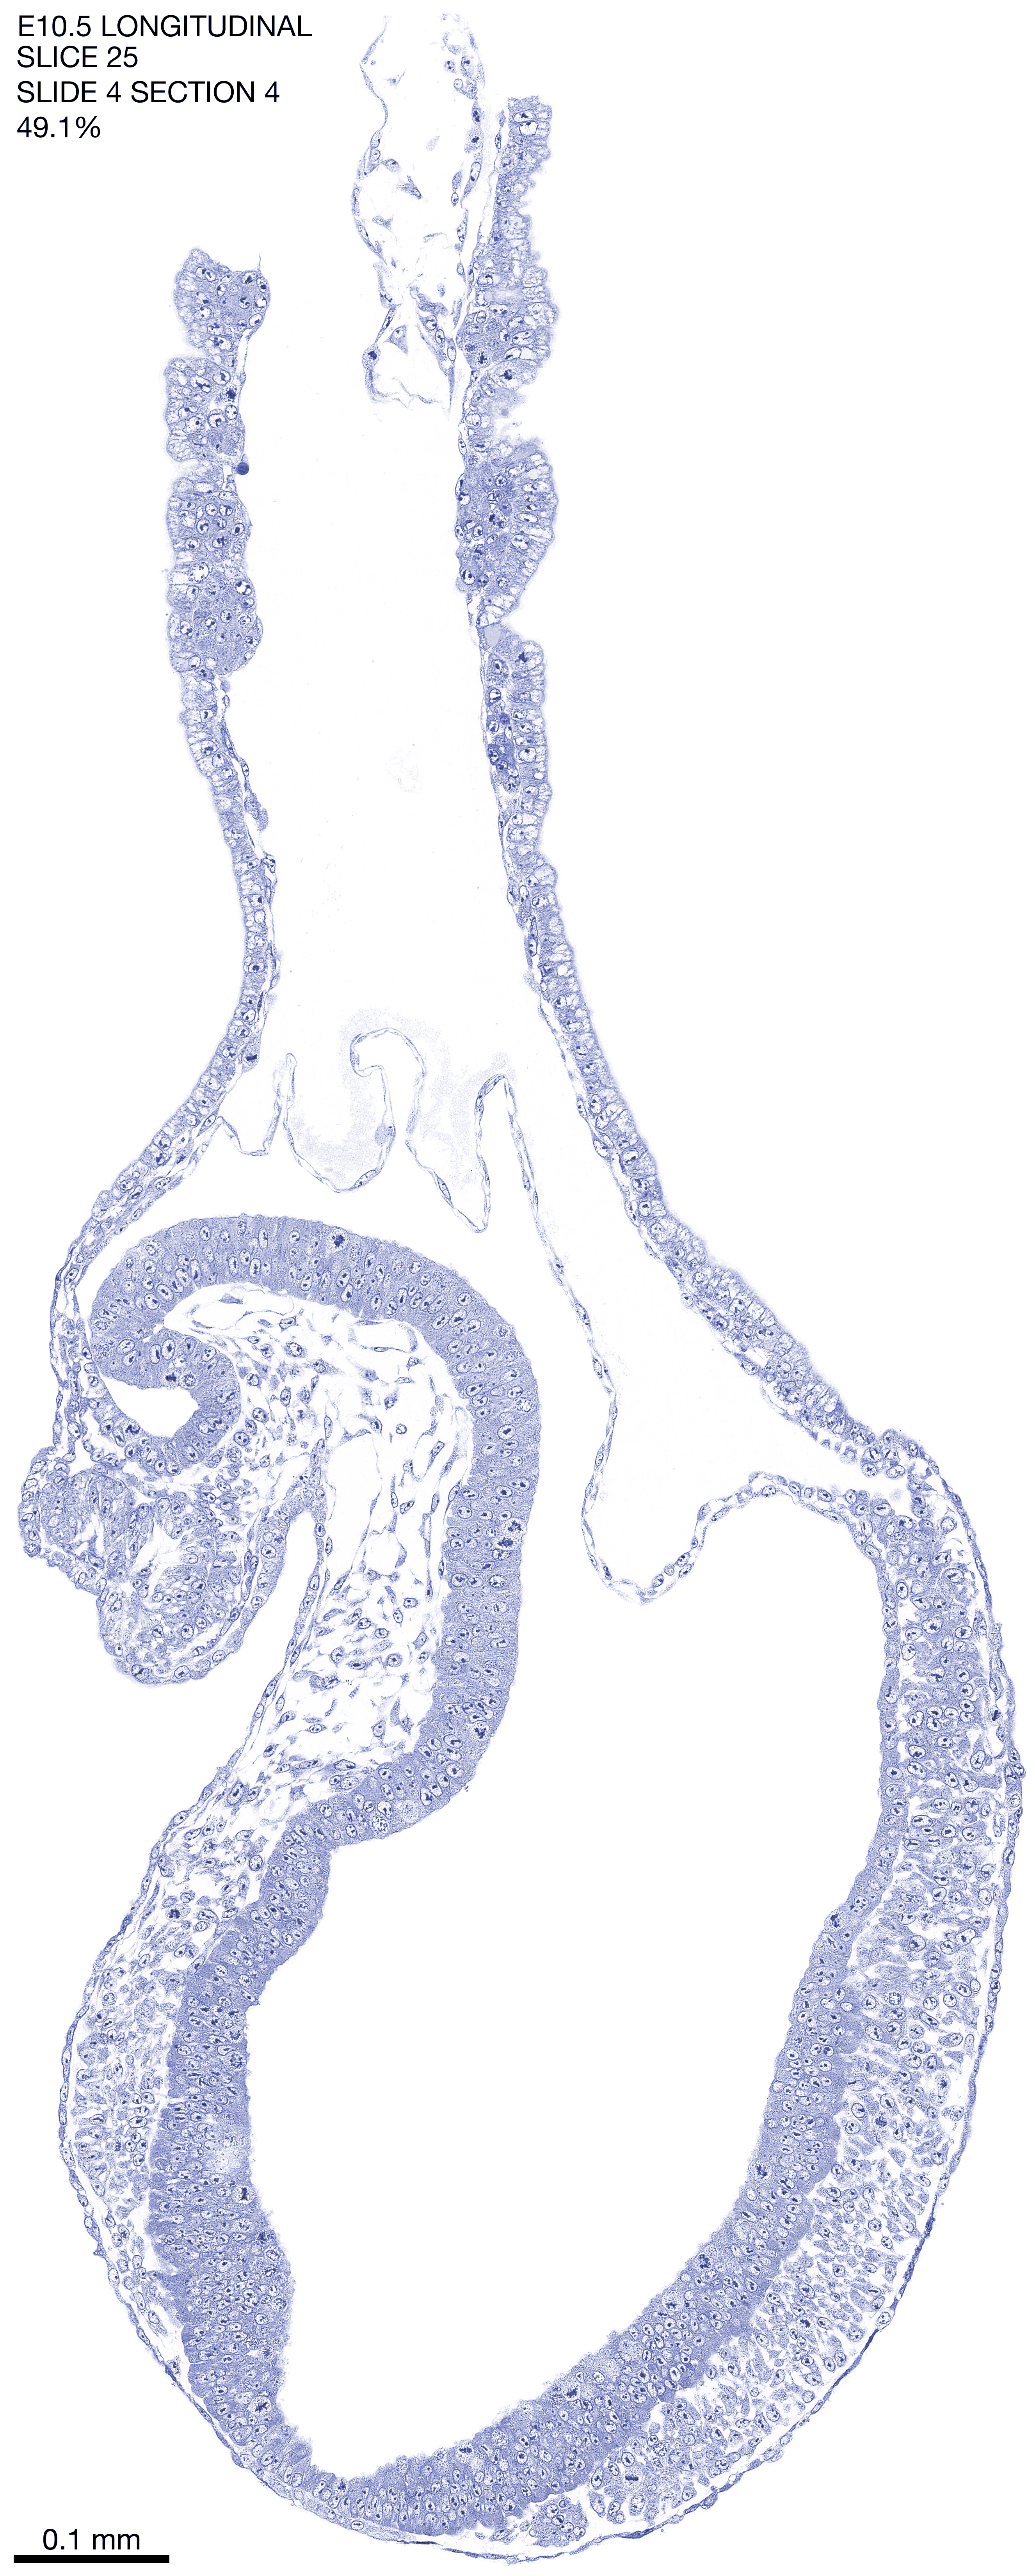

E10.5 Longitudianal Archive This page contains jpg files of ALL SLICES (each 3µm thick) that were scanned of the E10.5 longitudinally cut specimen. Download: Large | High Res Download: Large | High Res Download: Large | High Res Download: Large | High Res Download: Large | High Res Download: Large | High Res Download: Large | High Res Download: Large | High Res Download: Large | High Res Download: Large | High Res Download: Large | High Res Download: Large | High Res Download: Large | High Res Download: Large | High Res Download: Large | High Res Download: Large | High Res Download: Large | High Res Download: Large | High Res Download: Large | High Res Download: Large | High Res Download: Large | High Res Download: Large | High Res Download: Large | High Res Download: Large | High Res Download: Large | High Res Download: Large | High Res Download: Large | High Res Download: Large | High Res Download: Large | High Res Download: Large | High Res Download: Large | High Res Download: Large | High Res Download: Large | High Res Download: Large | High Res Download: Large | High Res Download: Large | High Res Download: Large | High Res Download: Large | High Res Download: Large | High Res Download: Large | High Res Download: Large | High Res Download: Large | High Res Download: Large | High Res Download: Large | High Res Download: Large | High Res Download: Large | High Res Download: Large | High Res Download: Large | High Res Download: Large | High Res Download: Large | High Res Download: Large | High Res Download: Large | High Res Download: Large | High Res Download: Large | High Res Download: Large | High Res Download: Large | High Res Download: Large | High Res Download: Large | High Res